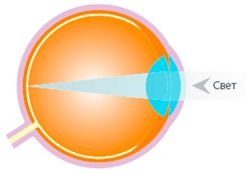

Суть проблемы в схемах

На первой схеме представлено здоровое глазное яблоко: свет фокусируется в макулярной зоне сетчатки, формируя четкое изображение.